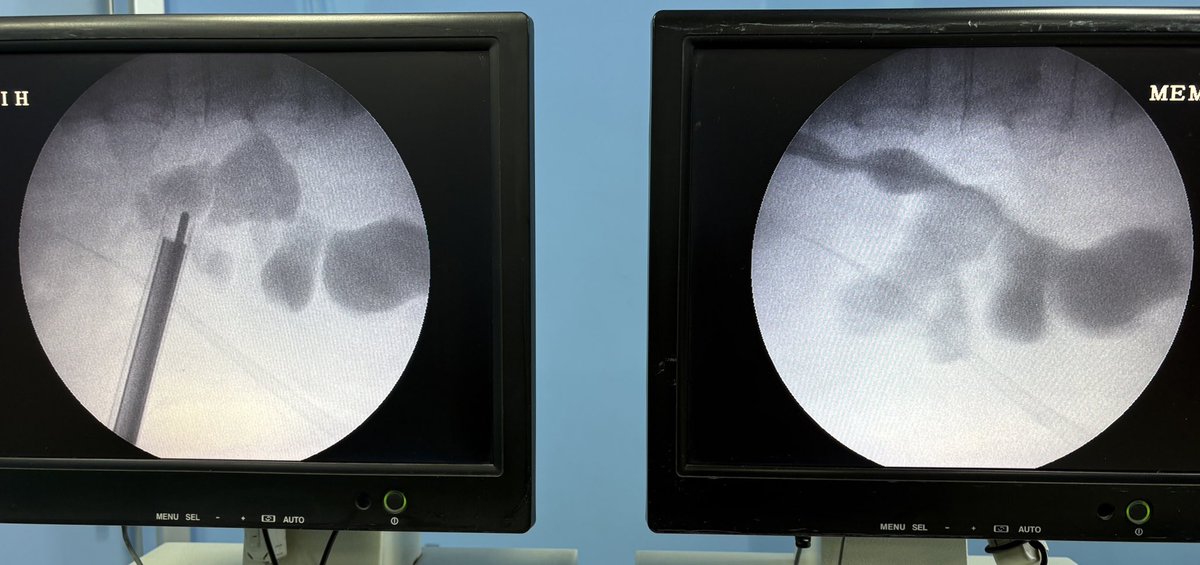

Large 45*25 mm partial staghorn calculus. HU 1100 My standard 22 F for the bulk And Mini 16 F for the secondary stones #supinepcnl Lithotripsy time 45 mins (pneumatic). What do you prefer in supine: small fragments and spontaneous expulsion or bigger fragments and graspers.